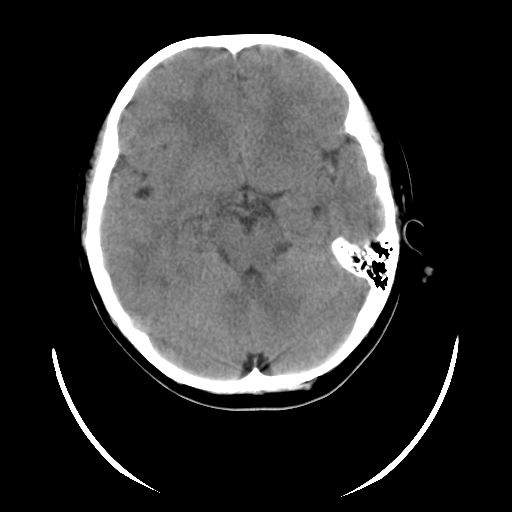

女,6岁,头痛、呕吐一天。